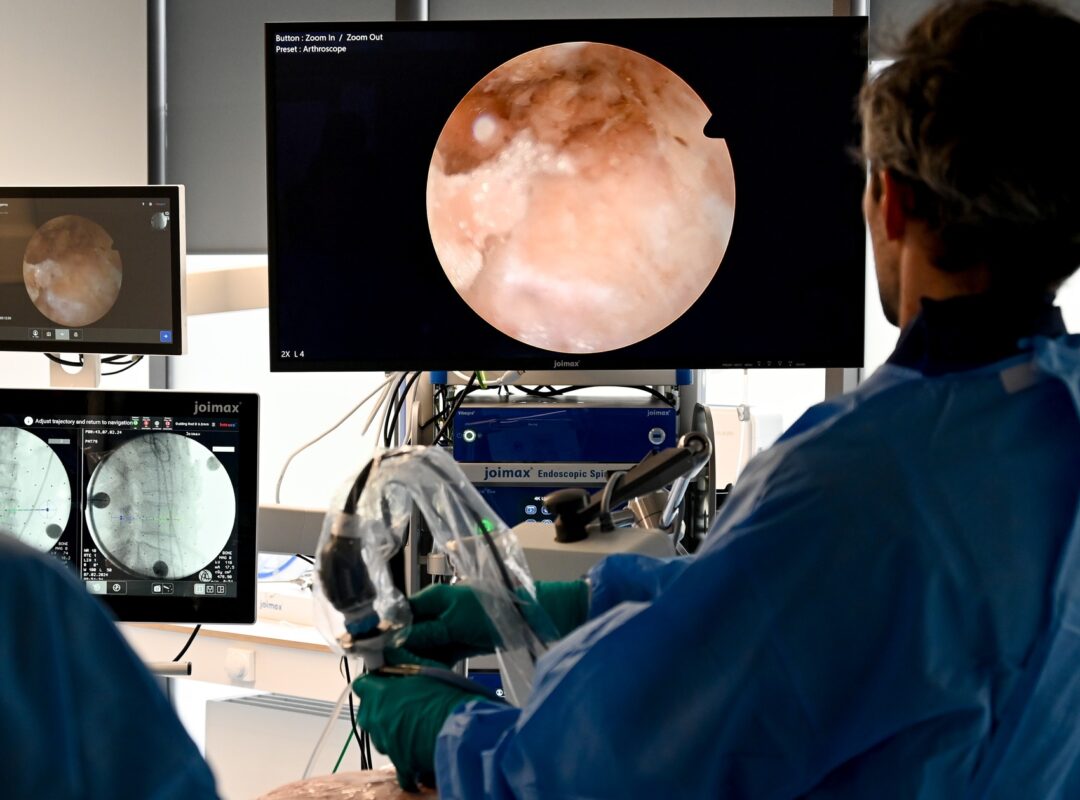

The imaging system is the heart of endoscopic spine surgery. A combination of high-resolution image processing and brilliant optical performance are necessary to safely navigate the anatomy of the spine and capture even the smallest structures. To achieve this, joimax® imaging components – from endoscope over camera to monitor – are developed not as individual products, but as a cohesive, integrated system – each with the goal of highest performance and clearest vision. Our latest 4K imaging solutions reveal even smallest details and create an almost spatial visual impression.

Perfect images to support endoscopic spine surgery – because illumination, optical system and image processing are ideally matched.

Our most recent endoscopes were designed with the latest camera technology in mind. The optics are optimized for 4K-resolution systems to offer the sharpest picture possible. The improved optical performance enables the user to clearly identify and differentiate even smallest structures.

Together with the 4K Camsource® LED, Camsource® Duo and the 4K UHD Display, joimax® offers a complete optical solution with superior image quality for endoscopic spinal surgery.